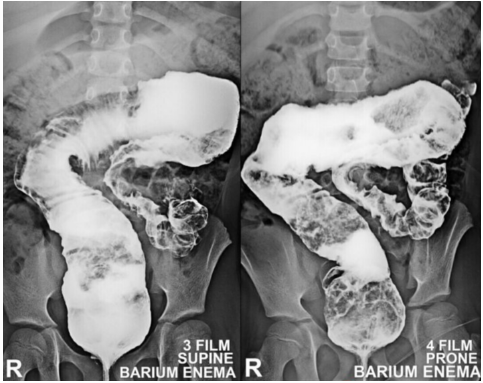

The given barium enema is suggestive of _____ disease

_____ appearance is the characteristic finding seen in Barium enema X-ray in a case of intussusception.